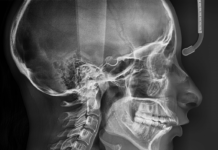

Телерентгенограмма — что за процедура и для чего она делается

Телерентгенограмма - это медицинская процедура, которая использует рентгеновские лучи для создания изображений внутренних органов и тканей пациента. Это важный диагностический инструмент, который позволяет врачам...